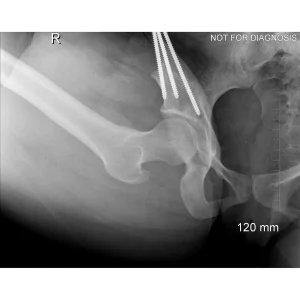

During a PAO, the surgeon carefully cuts the bone around the hip socket and repositions it to provide better coverage of the femoral head. The socket is then fixed in its new position using screws. The goal is to improve hip stability, reduce pain, and preserve the patient’s natural hip joint.

• Diagram 3: Hip After Periacetabular Osteotomy (PAO)

Diagram 3: Hip After Periacetabular Osteotomy (PAO)

• Acetabulum repositioned to improve femoral head coverage

• Load more evenly distributed across the joint

• Screws shown securing the acetabulum in its new position

These diagrams are commonly used in clinic to help patients visualize the problem and understand how PAO corrects hip mechanics. Dr Grammatopoulos will review your X-rays alongside these illustrations to explain your individual anatomy and surgical plan.